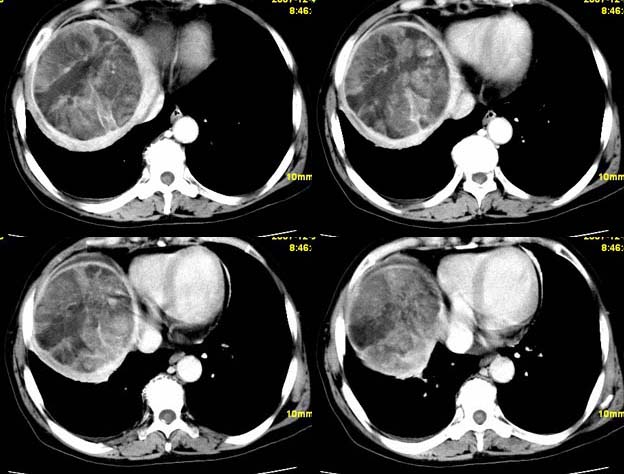

增强

支持;肝aml-------脂肪成分,中心血管征,延时强化.

以下是引用qiuleiyu在2007-12-25 21:20:00的发言:[br]支持;肝aml-------脂肪成分,中心血管征,延时强化.